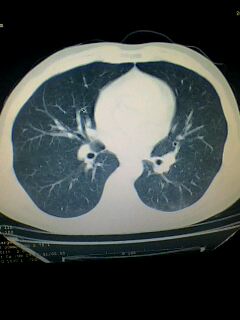

标题: CT28315:咳嗽咳痰咯血半月并胸痛 [打印本页]

标题: CT28315:咳嗽咳痰咯血半月并胸痛

左下肺肿块影,深分叶,考虑肺癌。

左下肺球形病灶,考虑:1:球形肺炎;2:周围型肺癌不除外,建议治疗后复查